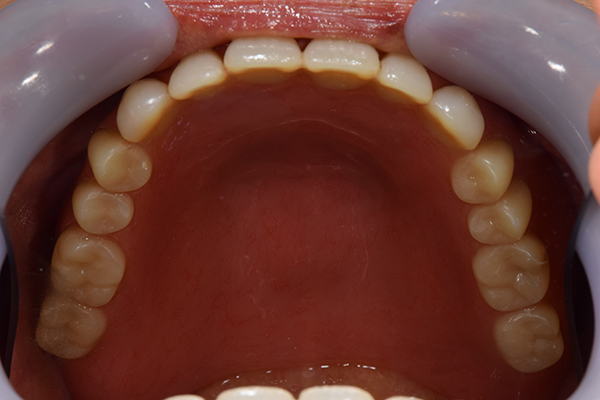

ケース2(自費の総入れ歯と部分入れ歯)

上下の入れ歯が外れやすくなったということでいらっしゃいました。 顎の骨はしっかりしていましたので、精密な型取りさえすればしっかりした入れ歯がつくれると思いました。 また下には6本歯が残っていましたが、虫歯になっている歯もありました。 かぶせ物のなかで大きな虫歯があった歯があり、1本だけ残せない状態でした。

上の入れ歯は確かに吸着は甘くなっていました。 また下の入れ歯はバネの一部が壊れており、安定感がなくなっていました。

精密な型取りの後、噛み合わせのチェックをしていきました。 かぶせ物も同時に作っていきました。

歯を並べた後、かぶせ物のフレーム作ってもらいました。先に歯を並べて理想の位置を決めておくことが大切です。

完成した入れ歯とかぶせ物です。 入れ歯への寛容度が高い患者様でしたので、 金属は使用せず、プラスチックのみで上は仕上げました。 下顎も歯は1本減ってしまいましたが、しっかり 入れ歯が維持できる様な構造にしました。

お口の中に入れた状態です。 見た目も最初とほとんど変わることなく作成できました。 維持や吸着に関しても問題ないようでした。

年齢 80歳・女性

主訴 上下の入れ歯が外れやすくなった

治療期間 3ヶ月

治療費 .メタルボンドクラウン:550,000円

.義歯:990,000円(税込、上下)

治療方針 長年使ってきた義歯の人工歯が磨耗し、臼歯部での咬合がすくなくなり、入れ歯の安定も悪くなり、あたりどころが悪くなって痛みが出ている。 そのため、入れ歯を上下作りかえる必要がある。

治療内容 過去に治療を行ったことのある歯が再度虫歯になってしまっているところがあり、すでに残せない状態にまでなっていたため、歯を一本抜歯した。 その後、かぶせ物と入れ歯を同時に作成していった。

特記事項 歯を抜いた後は、2〜3ヶ月歯ぐきの回復を待ってから入れ歯を作るため、待機期間があります。その間、古い入れ歯を調整しながらそのまま使うか、新し物をつくっておく必要があります。ただし、入れ歯は保険治療で作成する場合、6ヶ月は新しいものが作れないという決まりがあるので保険で全て作りたい場合は注意が必要です。